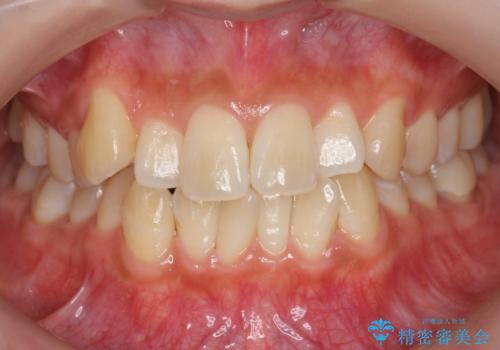

[ 総合歯科診療 ] がたつきの改善とセラミック治療

![[ 総合歯科診療 ] がたつきの改善とセラミック治療の症例 治療前](https://seimitsushinbi.jp/wp/wp-content/uploads/2024/03/f0f438a14c56b185411649f48b5b188c-500x350.jpg?v=1710833163)

![[ 総合歯科診療 ] がたつきの改善とセラミック治療の症例 治療後](https://seimitsushinbi.jp/wp/wp-content/uploads/2024/03/7212917eb9c4ef33050c52e7f9724490-500x350.jpg?v=1710833188)